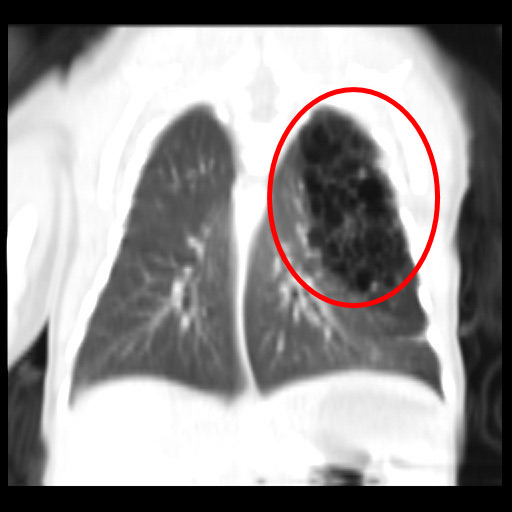

「先天性肺部呼吸道畸形」是指肺葉被類似囊泡樣的組織取代,而沒有正常的肺泡,無法進行氣體交換,甚至壓迫到縱膈腔造成心臟血管偏移,發生率大約是每25000~35000名新生兒中會出現一名,十分罕見。兒童外科楊筱惠醫師表示,小敬媽媽做產檢時並未發現異常,且生產過程順利並無早產,但小兒主治醫師張宇勳主任和照護小敬的醫護團隊十分警覺,發現孩子出生後出現呼吸喘的情形,很快地被轉往新生兒加護病房(PICU)並做X光檢查,從影像中發現小敬的左上肺葉有一些「囊泡」模樣的東西,判斷這可能是「先天性肺部呼吸道畸形」,於是後續再幫他做電腦斷層,確定符合診斷。

根據先天性肺部呼吸道畸形的嚴重程度差異,個案會有不同的症狀表現,有些非常嚴重的個案,當胎兒還在媽媽肚子裡,就已呈現嚴重水腫,甚至出生後很快地死亡,或者是會喘到需要插管或裝上葉克膜。所幸小敬的呼吸喘情形並沒有太嚴重,加上他的左下肺葉發育得很好,僅需要正壓呼吸器的輔助即可。楊筱惠醫師指出,產檢發現而出生後無症狀的案例是否手術切除仍有爭議,但對於有症狀、呼吸喘的寶寶,則需手術將無正常功能的肺葉切除;人體共有五片肺葉(左二、右三),由於觀察到小敬的其他肺葉發育良好,經過醫療團隊和家屬討論,決定盡快為小敬動手術,盡早把生病的左上肺葉切除掉,這樣可以讓正常的肺葉進行功能上的代償,對孩子日後的呼吸能力影響也較小。